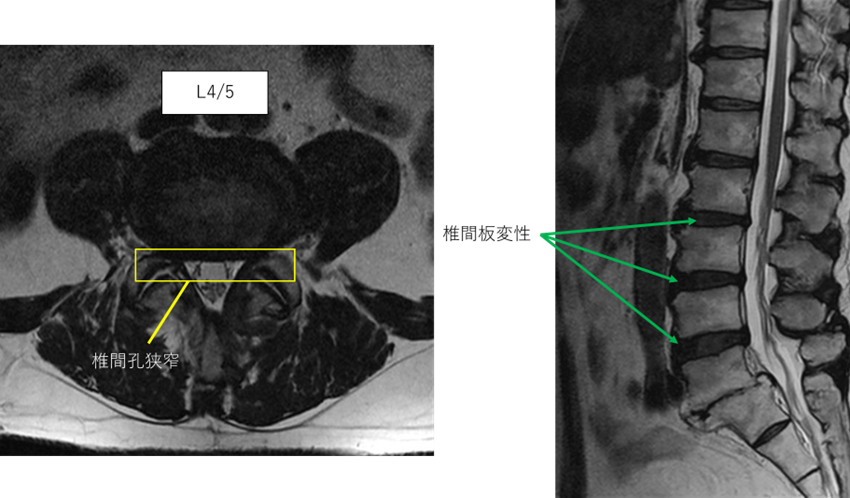

画像及び所見について

L1/2: 異常なし

L2/3: 椎間板変性症

L3/4: 椎間板変性症

L4/5: 椎間板変性症、両椎間孔狭窄

L5/S: 椎間板消失

以上の事が画像上認められます。

L2/3.3/4.4/5に

椎間板変性症、椎間孔狭窄を認め、主症状の原因の可能性が高い。